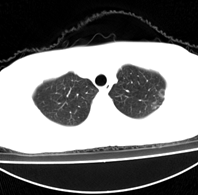

病人为一考上研究生的学生,健康体检发现。请踊跃发表意见。

左肺上叶见后段近侧胸壁见两个薄壁空洞影,洞内无液平,考虑肺囊肿,因为肺囊肿位于肺的外周,囊肿与支气管相通,囊壁薄,囊内无液性成分。以上使我的观点,原与各位交流

左肺上叶尖后段胸膜下可见两个类圆形薄壁空洞,内外壁较光滑,腔内为气体密度,支持结核性薄壁空洞。

我想应是肺囊肿,因为边界清晰,其内无液平面,周边没有卫星灶,还有临床也不支持肺结核

临床无症状,左上肺两枚厚壁空洞,内无气液平面,周围未见卫星灶,囊肿可能大,建议追问病史。请各位老师指正

左飞上叶尖后段两个含气的囊性肿块,边界清晰,其周围未见卫星病灶,考虑肺囊肿.不支持肺结核是因为未见卫星灶,临床未见体征.

左肺上叶后段见两个孤立圆形厚壁空洞,无液平及壁结节。周围清晰,无卫星灶。结合病史,如此大的病灶病人毫无感觉,另外周围如此清晰,应能排除结核空洞;肺囊肿壁应更薄,如合并感染可增厚,但周围应模糊。本人考虑:肺韦格肉芽肿。

左肺上叶后段见两个孤立圆形厚壁空洞,无液平及壁结节。周围清晰,无卫星灶。结合病史,如此的病灶病人毫无感觉.考虑1肺部感染[注意新隐球菌感染----中华放射学杂志---2006----第一期-----104页]。2肺囊肿。请指教!!!

左上叶尖后段可见两个中等壁厚空洞,腔内无液平,内外壁光整,局部轻度胸膜增厚,首虑结核。

考虑肺囊肿可能性大。不支持结核是因为周围肺野内未见明显卫星灶及纤维索条,不支持韦格氏肉芽肿是因为内壁及外壁均很光整,壁厚薄一致,而韦格氏肉芽肿洞壁厚薄多不均匀,内壁多不规则,其内可有形态不规则的内容物。

左肺尖后段的两个薄壁(纵隔窗)含气囊样病变,壁厚薄较均匀、光整、内无液气平形成、其邻近肺野见

少许渗出、未见卫星灶,其余肺野未见明显支气管播散灶(楼主虽然未上传全其他层面图片,但认为因正常而未上传)。

综合上述:考虑为肺囊肿合并感染,不支持结核空洞(虽然病变位于结核好发区,但认为这么明显的结核空洞应该有明显的肺内支气管播散灶)。